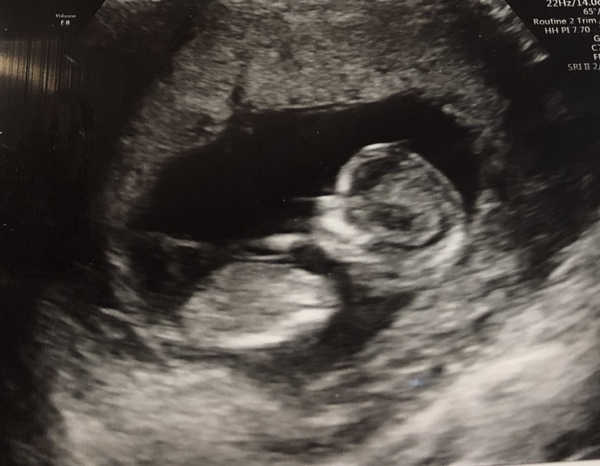

Curlywurlywoo · 24/01/2019 12:22

Just had my scan! I was so nervous before I was shaking, and so relieved now that I could sleep all day! I had to wee twice as I had drank too much 😂 and the baby was bottom in the air, then it was upside down and wouldn’t get into the right position but eventually we got there! All ok! I was half convinced there would be a problem or nothing in there as I’ve had so little in the way of symptoms, but there he/she is! X

@Curlywurlywoo @sunshine1987 both amazing photos congratulations!!

I was told I’m measuring a day more than I was, but that some babies are just bigger/smaller. Nurse said due date 28th July based on that, but my midwife said August 2nd..my mum went two weeks over with both me and my sister so if it’s ok I’ll stay in this group? Please 😊

@Curlywurlywoo @sunshine1987 fabulous scan pics! Oh definitely stay with us 😊

Lovely photos @Curlywurlywoo and @sunshine1987 😍